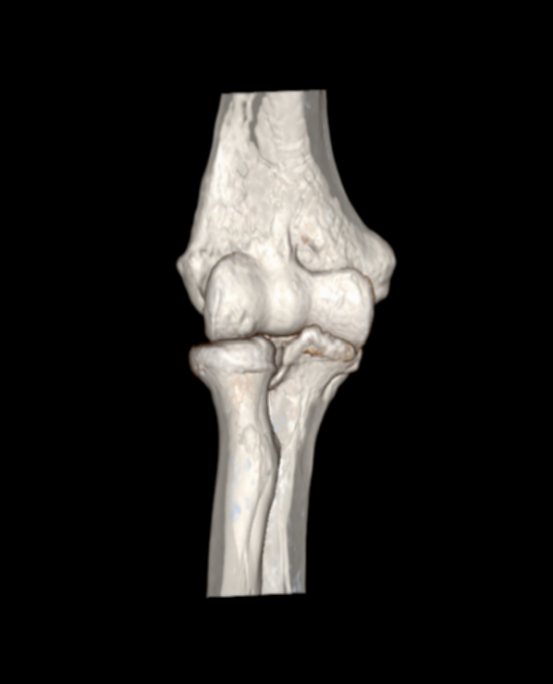

近日,一位52岁的男性患者,因右肘疼痛伴活动受限2周余来pilipili 就诊。经检查,确诊为肘关节骨性关节炎伴游离体。患者于入院第二天在气管插管麻醉下行右肘关节镜探查+滑膜切除+游离体取出术。术后症状明显缓解,疼痛减轻,关节活动范围改善,现已成功出院。

患者鹰嘴骨质增生;前侧关节腔游离体形成

术后CT、DR提示游离体取出